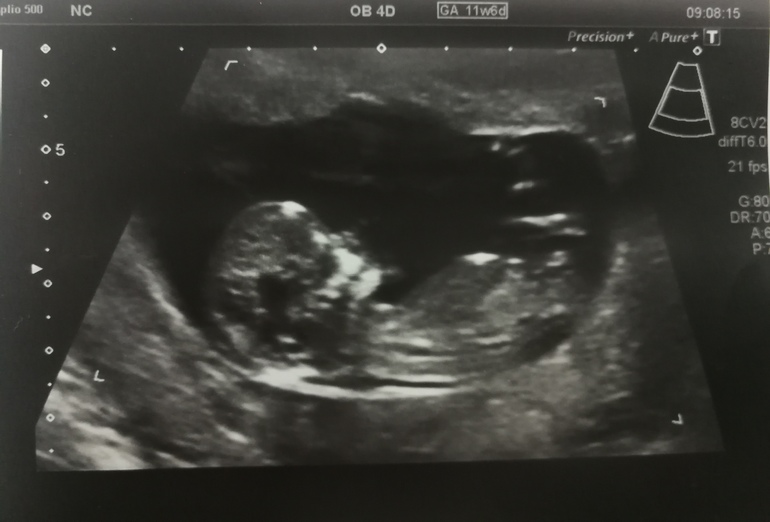

Я БЕРЕМЕННА !Привет всем! Ездили сегодня на скрининг в Кулакова. Вот так вот после 4х лет бесплодия: лапары, гистеры, гормональной терапии и двух ЭКО, мы победили. Со второго свежего протокола получился у нас симпатичный здоровый мальчик (точнее, Белоусов сказал "категорически большая вероятность, что это мальчик"👶). Картинка даже нам с мужем показалась довольно очевидной😀 Белоусов очень милый был, шутил, рассказывал про малыша. Я просто мнительная, и на бесплатный скрининг от ЖК побоялась ехать, ляпнут там чего-нибудь. Решила, что нужно ехать платно к проверенному врачу. Не пожалела.

Да вообще, бластоцисту переносили, которую под микроскопом еле видно, несколько клеток... всего лишь навсего 13го ноября. 2 месяца и уже парень вырос👶